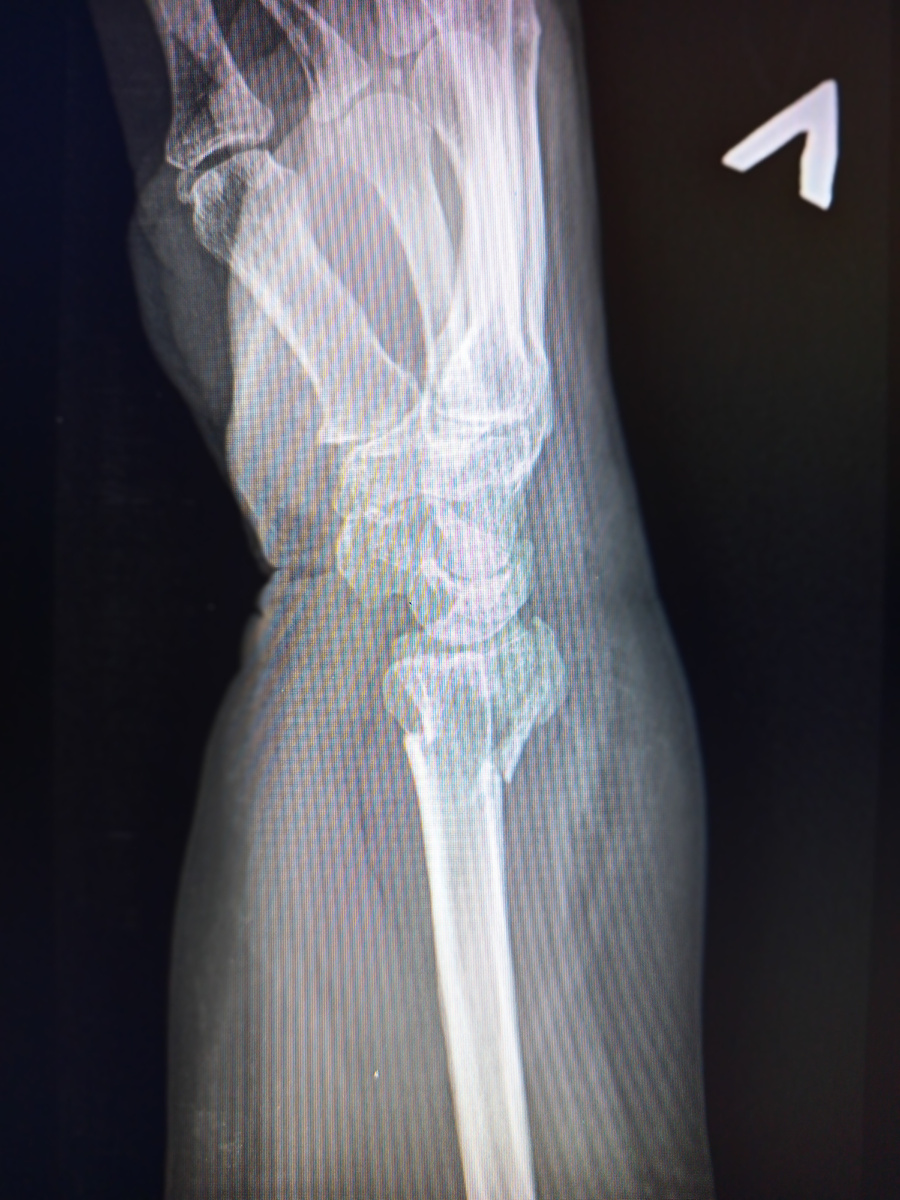

Да , луч сломала.Можно каждый денек благодарить, на протяжении месяца полтора , как минимум)

И шиловидный еще до кучи

Еще одна лыжница пожаловала) Врезалась рукой во дерево

-3

Вывих , почти как" лайк" получился снимок.